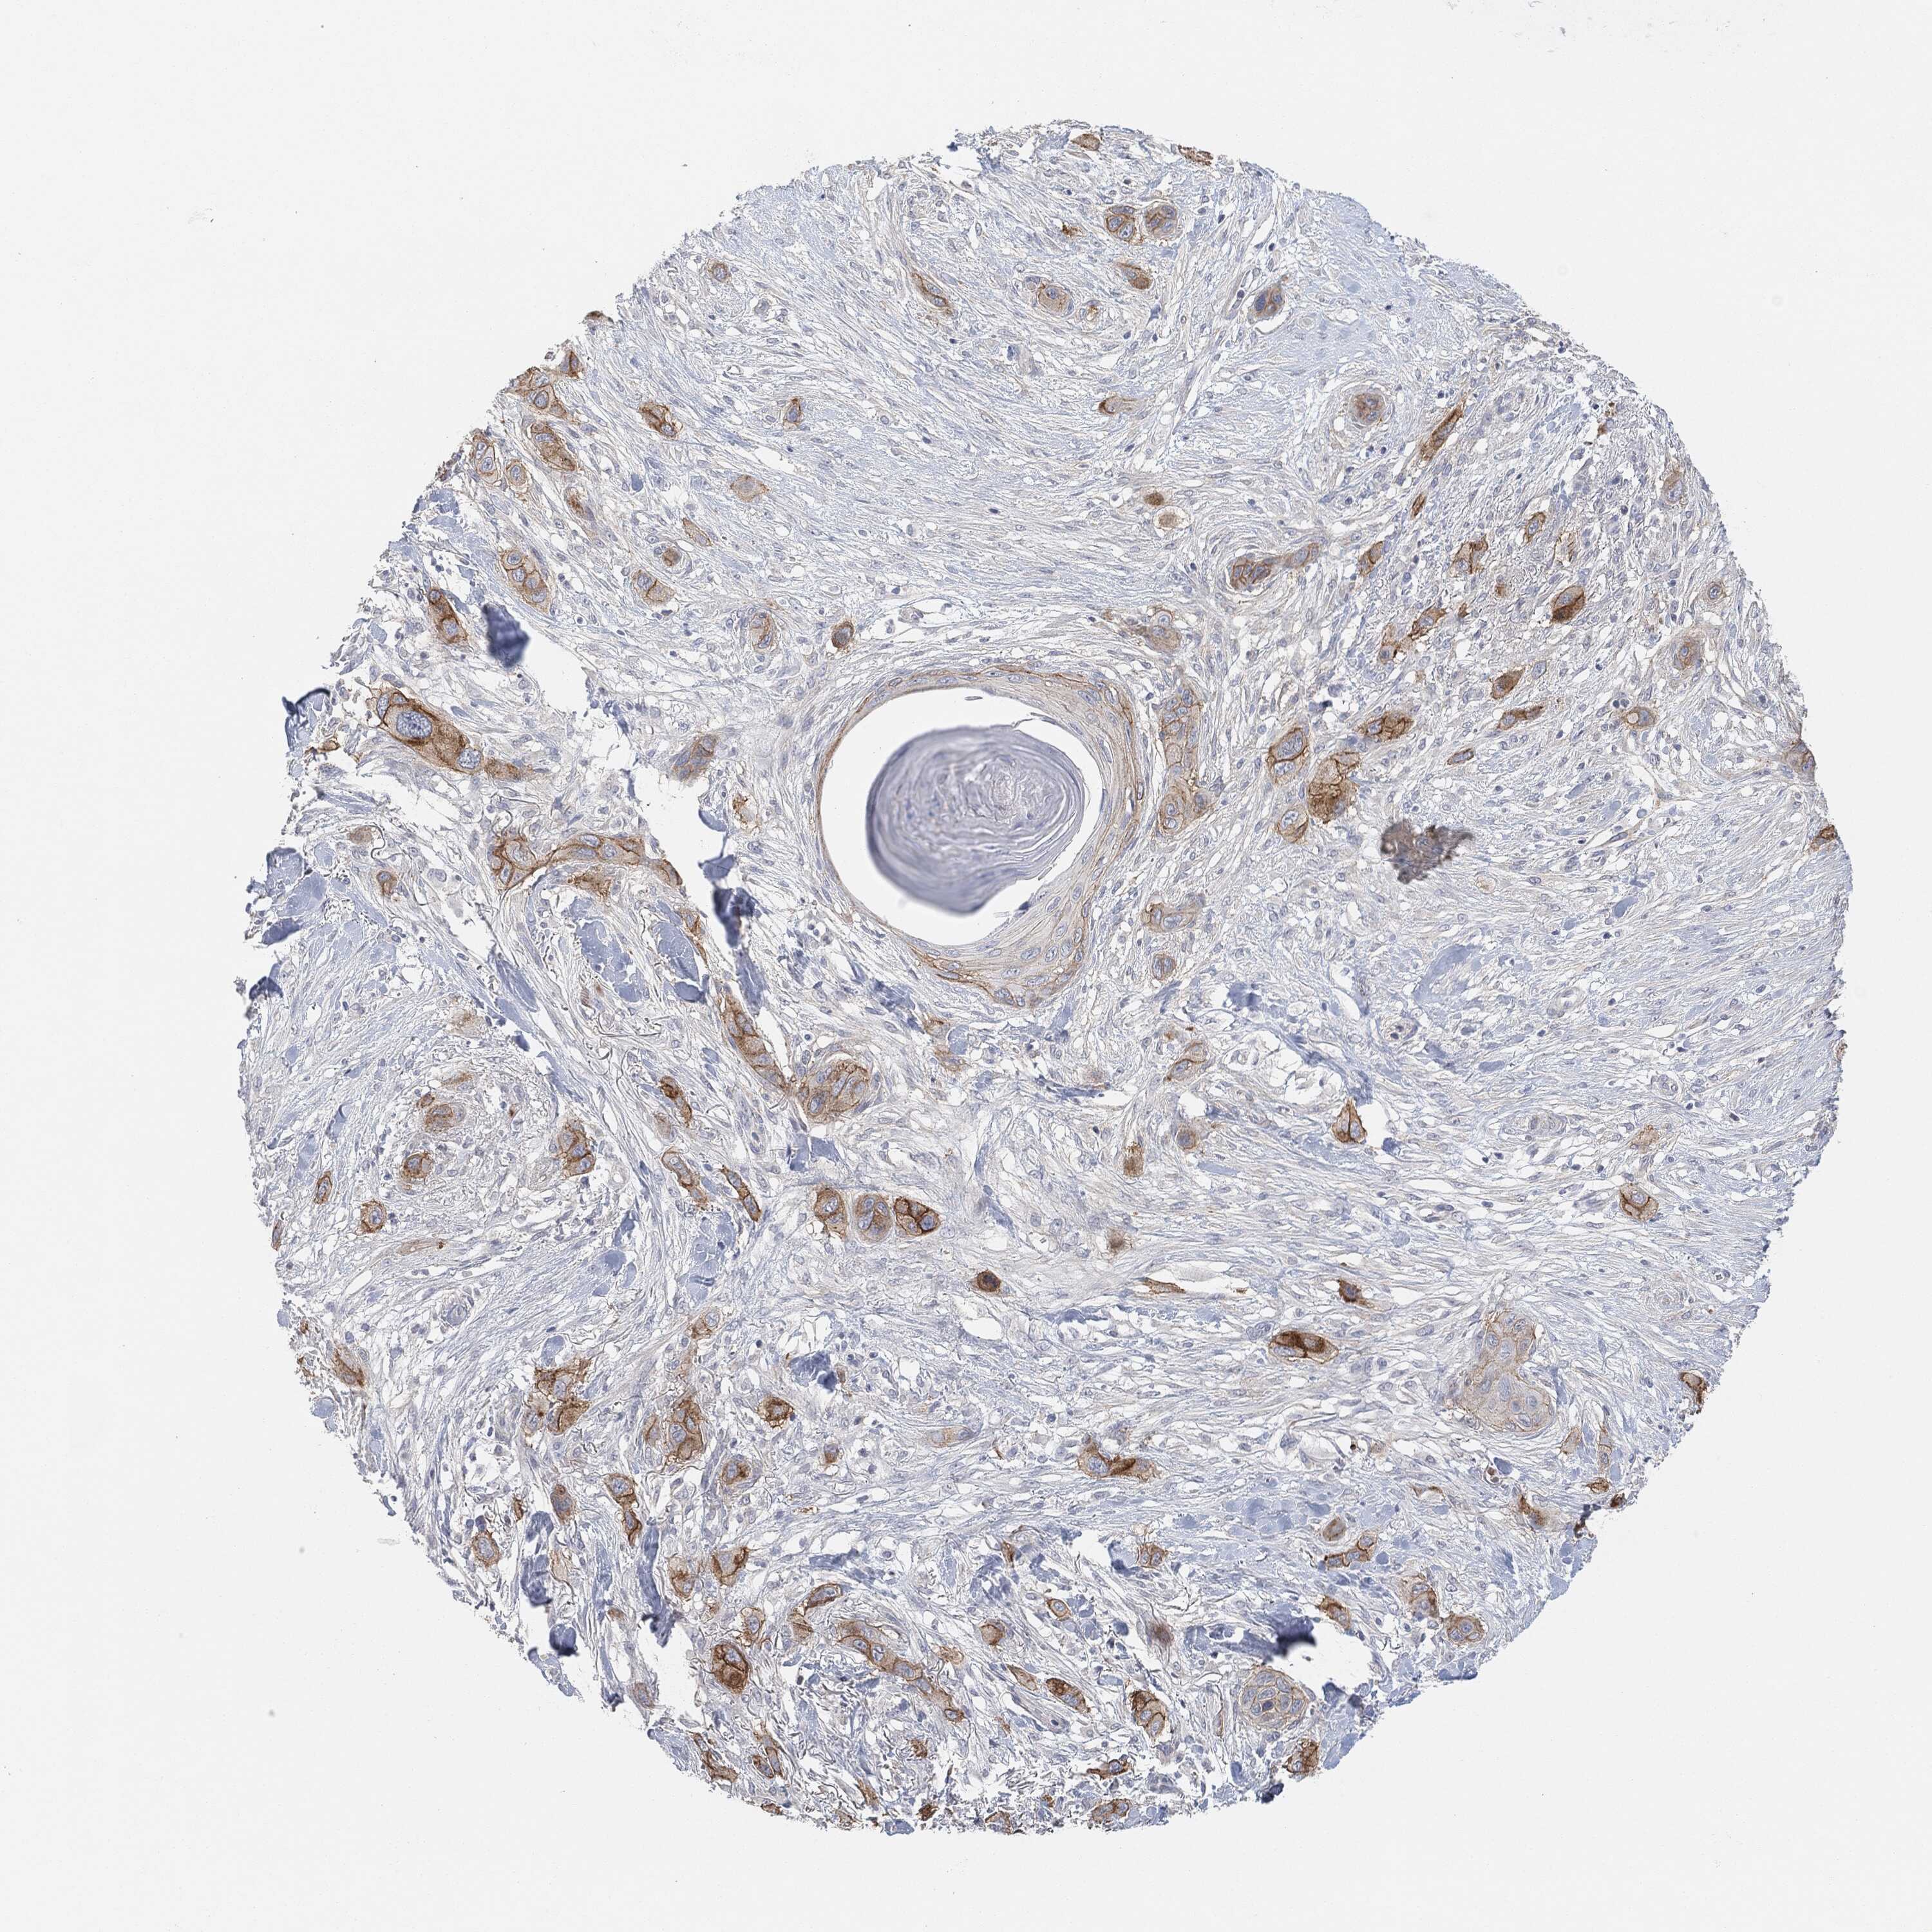

SKIN CANCER - Protein expressioni

A mouse-over function shows sample information and annotation data. Click on an image to view it in a full screen mode. Samples can be filtered based on level of antibody staining by selecting one or several of the following categories: high, medium, low and not detected. The assay and annotation is described here.

Antibody stainingi

Antibody staining in the annotated cell types in the current human tissue is reported as not detected, low, medium, or high, based on conventional immunohistochemistry profiling in selected tissues. This score is based on the combination of the staining intensity and fraction of stained cells.

Each image is clickable and will lead to virtual microscopy that enables deeper exploration of all samples and also displays staining intensity scores, fraction scores and subcellular localization as well as patient and tissue information for each sample.

Squamous cell carcinoma, NOS

Basal cell carcinoma

Squamous cell carcinoma in situ, NOS

Squamous cell carcinoma, metastatic, NOS